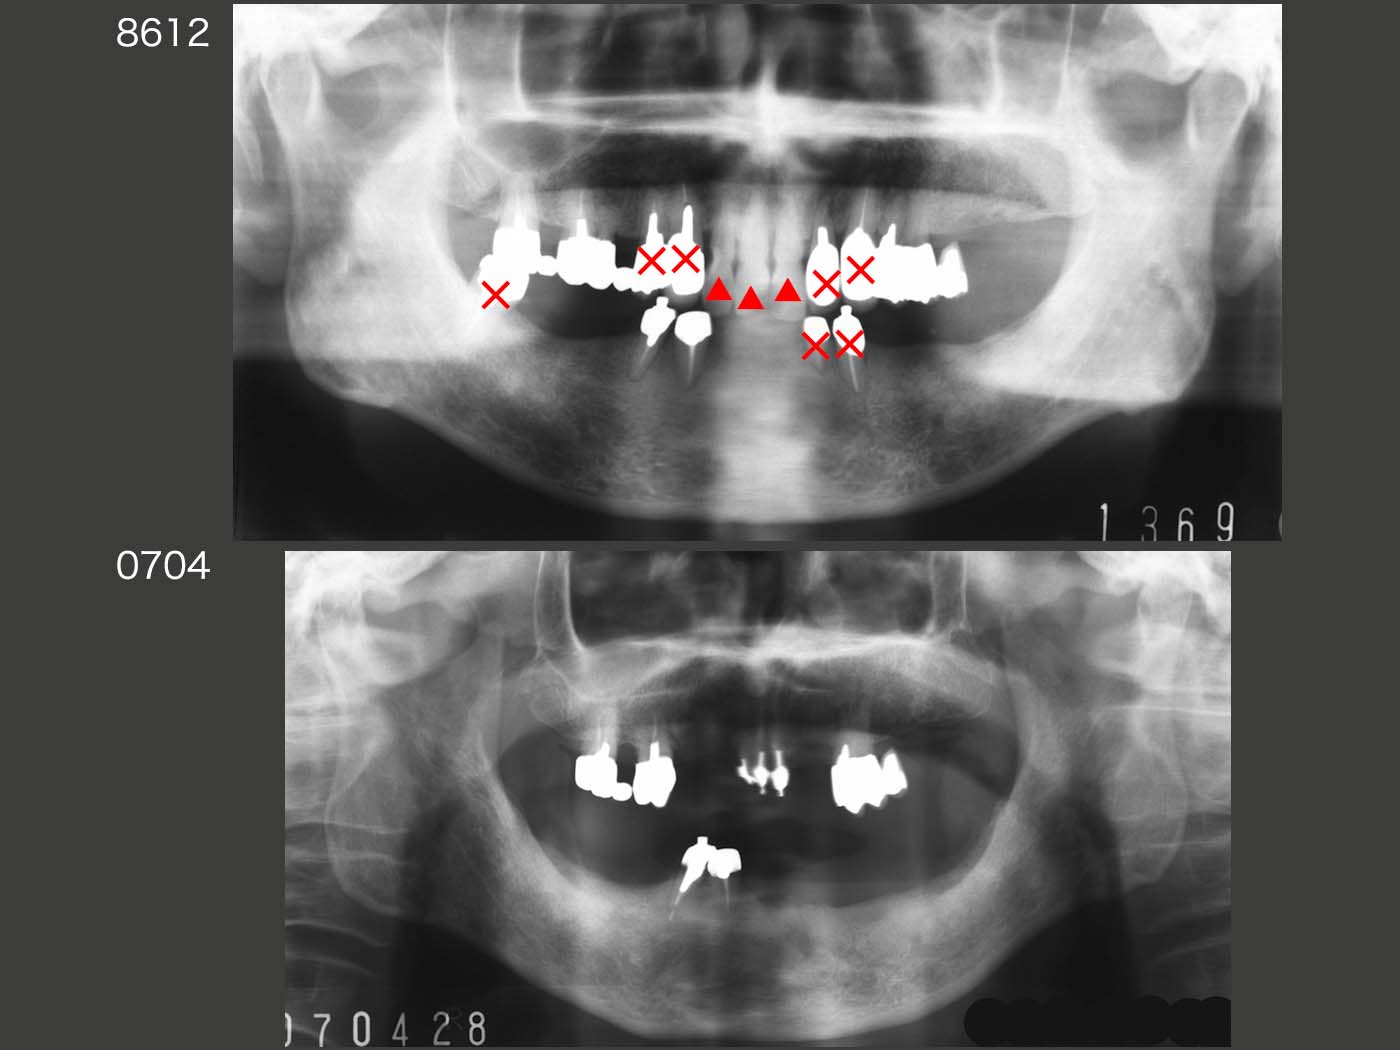

1986年初診終了時と,2007年初診終了後20年4ヵ月を比較したパノラマX線写真.赤印の×は抜去した歯であり,△印は歯冠破折した歯である.このスライドをみて明らかなのは,咬合支持歯に将来トラブルが生じるという事実であろう.一般的には上下の咬合支持歯同士でいわば勝負の形となってしまい,一方が抜け,もう一方が残るというようなことを多く経験している.しかし,残った方に全くダメージがない訳ではなく,今回の症例のように,最終的に双方が喪失してしまうこともある.一方,左上の延長ブリッジのように,力学的には不利であっても,そこであまり咀嚼せず,良く磨いていれば長持ちする.

結局,いくら上手なパーシャルデンチャーを装着しても,人は上下に歯があるところで主に咀嚼してしまうのである.やはり,咬んでいるという食感・美味しさを求めているのであろう.したがって,我々歯科医の最も重要な仕事は,歯根膜のある歯を抜かないことである.(加圧要素が強く,相対する顎堤の吸収が大きい場合は積極的に抜去することもあるが)また,特に咬合力の強い人は咬合支持歯がトラブルになるという前提にたって,治療方針を立案する必要があると痛感する.